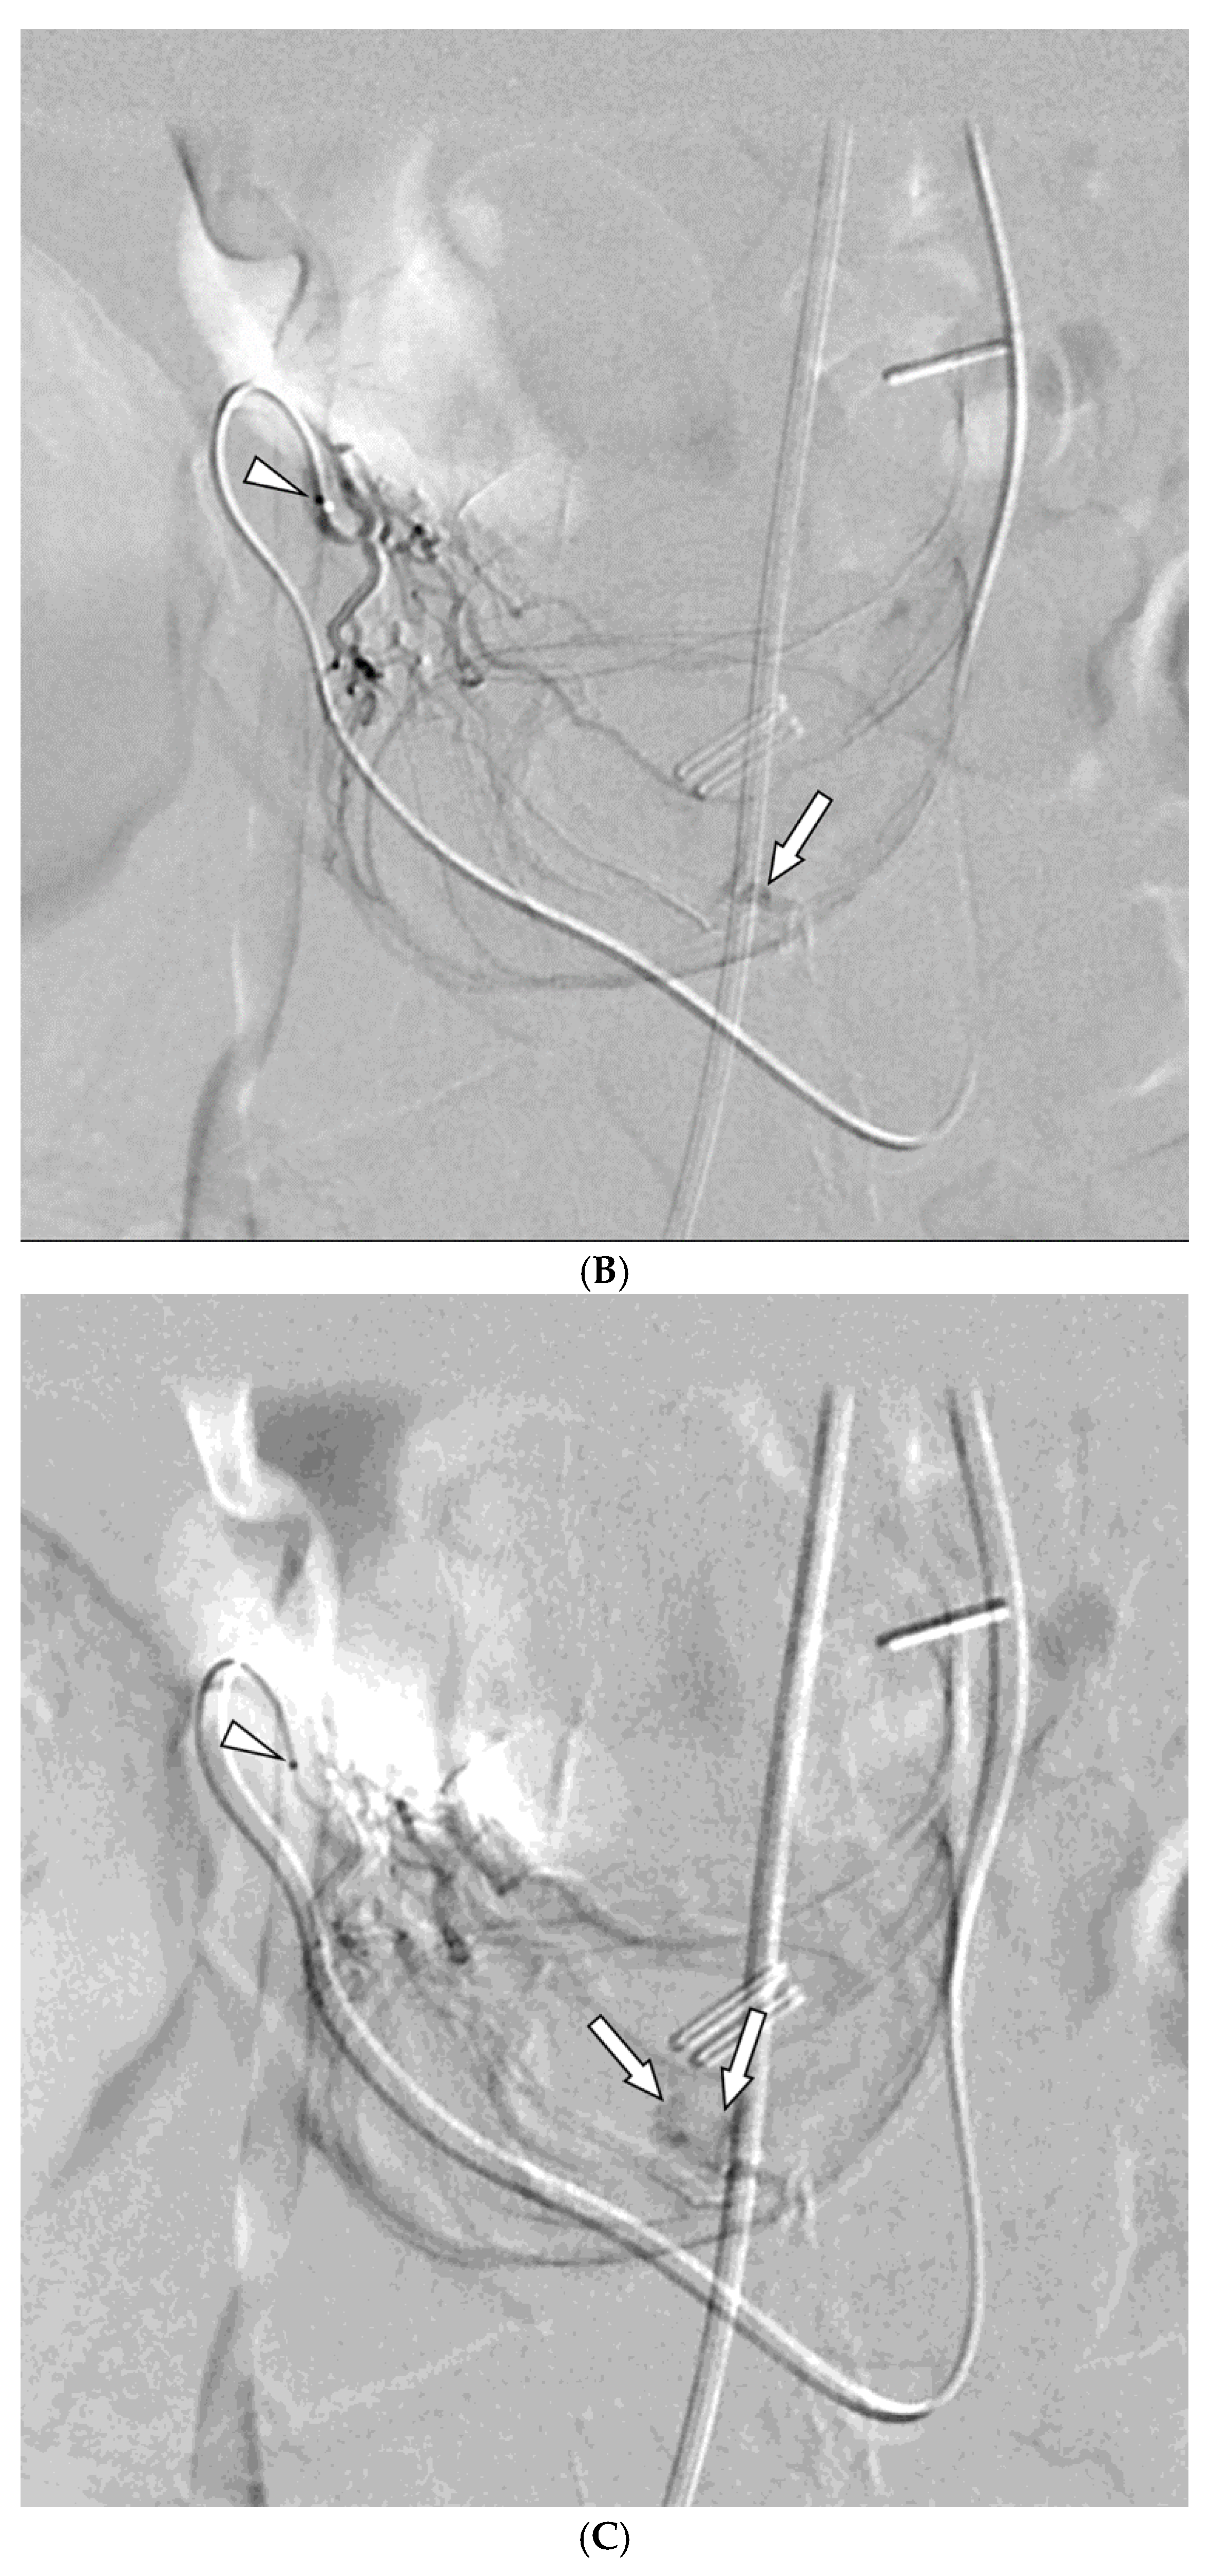

Figure 2. A 67-year-old woman presented with hematochezia. (A) Contrast-enhanced coronal CT image shows luminal contrast extravasation (arrow) at the jejunal loop. (B) Selective jejunal arteriography shows contrast extravasation (arrow). (C) Several levels of the vasa recta (arrows) were embolized with quick-soluble gelatin sponge particles (150–350 µm). (D) Post-embolization arteriography shows devascularization of the previously embolized vasa recta. No further bleeding occurred before the patient’s death one month after embolization.